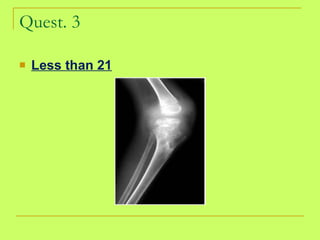

Quest. 3 Less than 21

What is the age? <21 knee